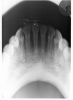

The selection of receptor sizes used in a full mouth series also varies. A full survey can consist of narrow anterior (type 1); standard adult (type 2); type 2 bitewing or long bitewing (type 3) (Figure 4) and may include anterior bitewings. It is generally recommended to use twenty radiographic images --- four bitewings and sixteen periapical images. Eight anterior type 1 radiographic images will allow for ease of receptor placement on patients with narrow palates. However, in some cases six anterior periapical images will cover the area needed.

Figure 4 - Intraoral Receptor Sizes

Figure 4